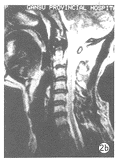

图2a X线片反映为C2椎弓根部骨折。

图2b MRI矢状位几乎无任何变化。